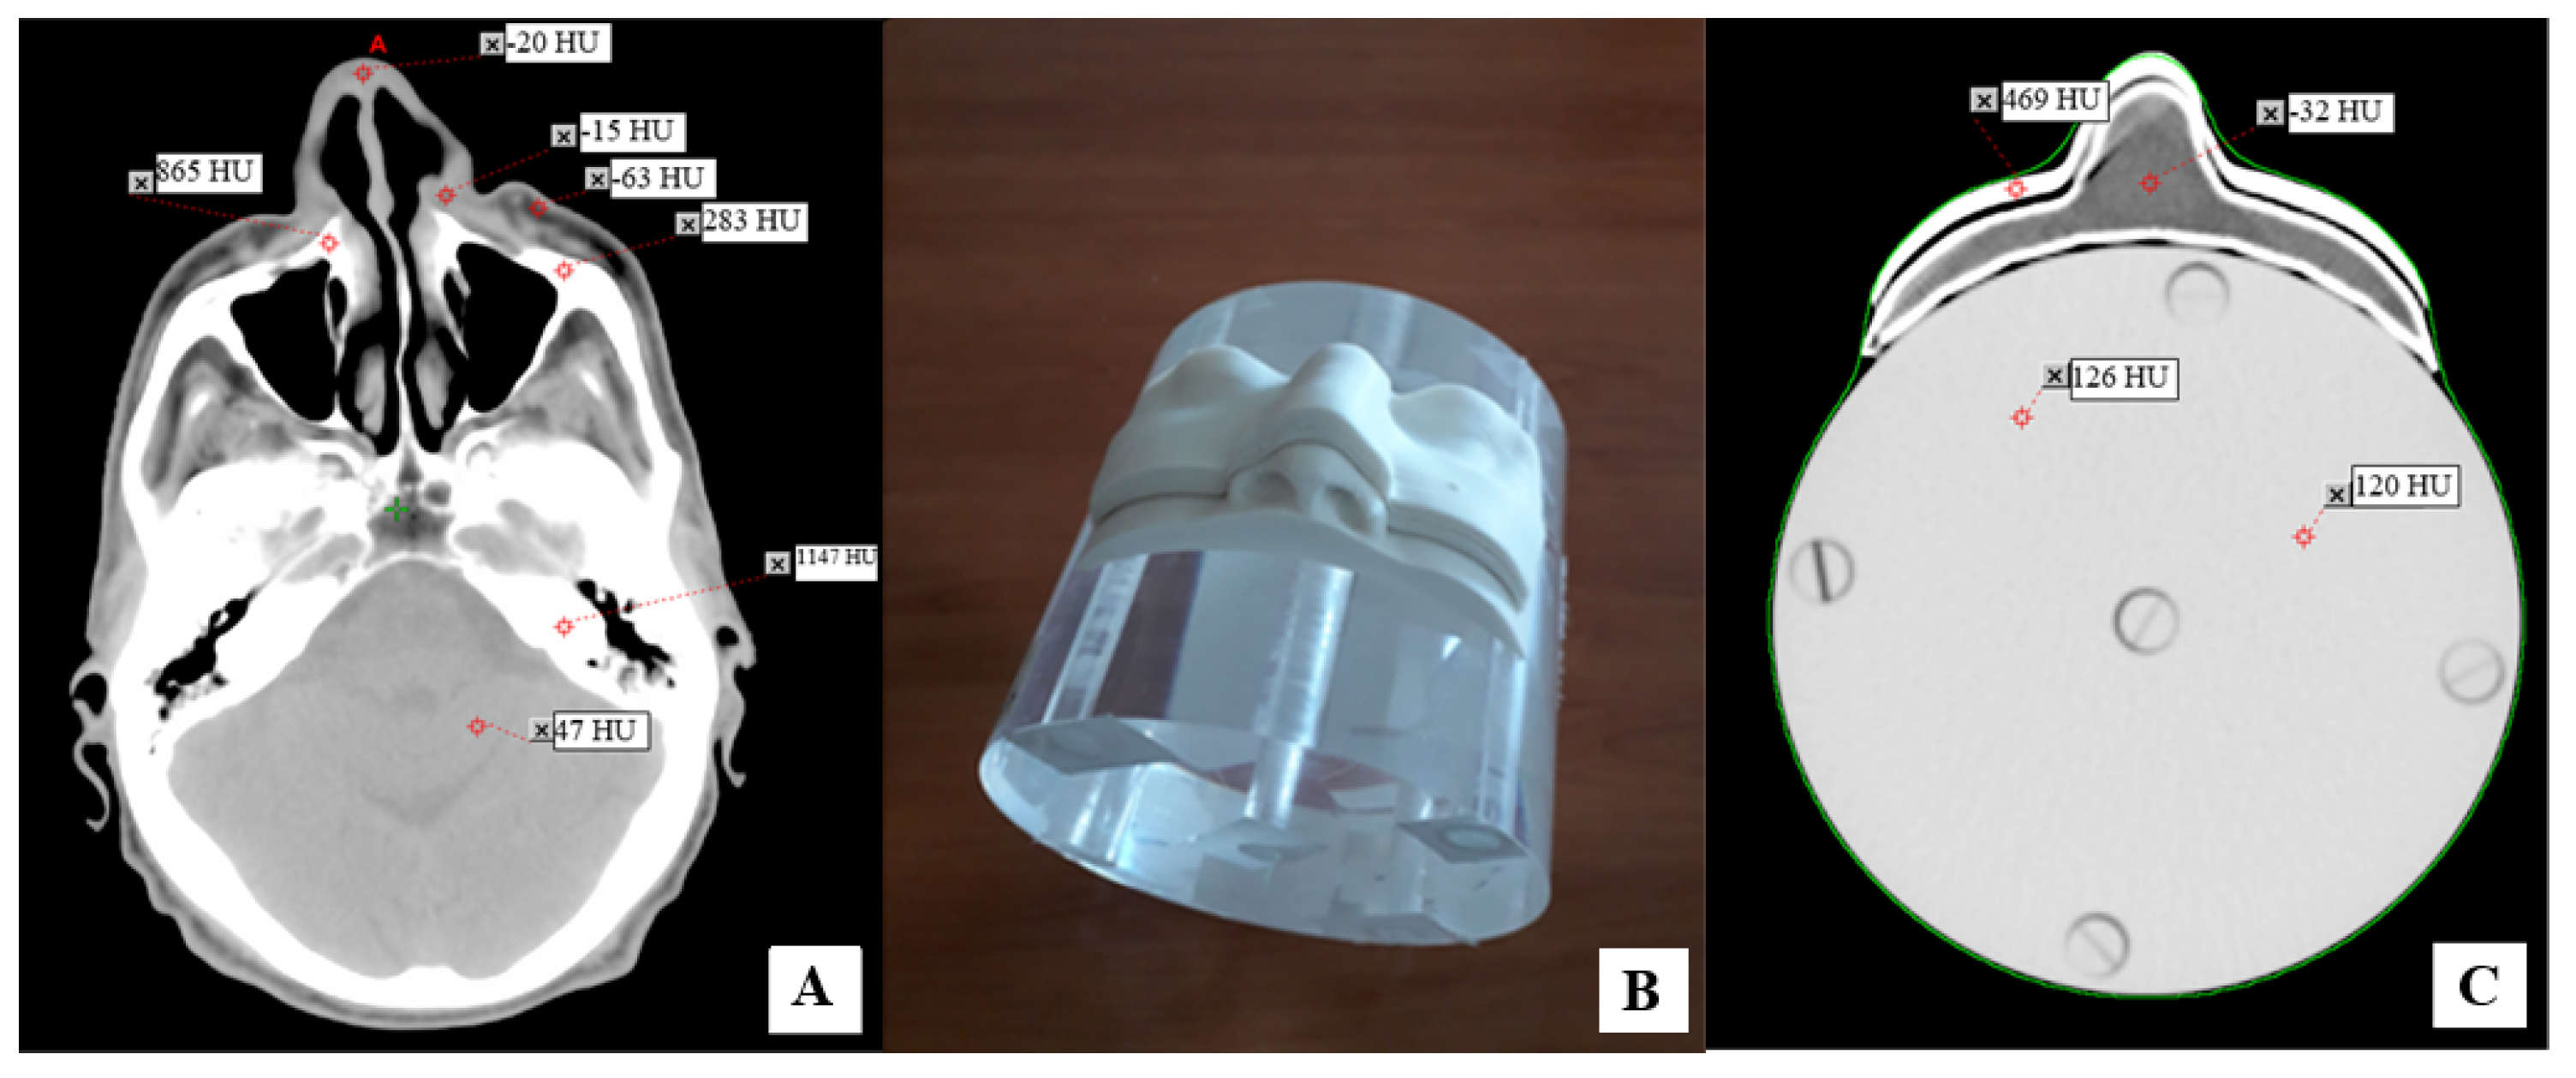

2.1. Development of Personalized 3D Devices

2.2. Physical Characterization of 3D-Printed Objects

3.1. Physical Characterization of 3D Printed Objects

3.2. Conformity of 3D-Printed Bolus